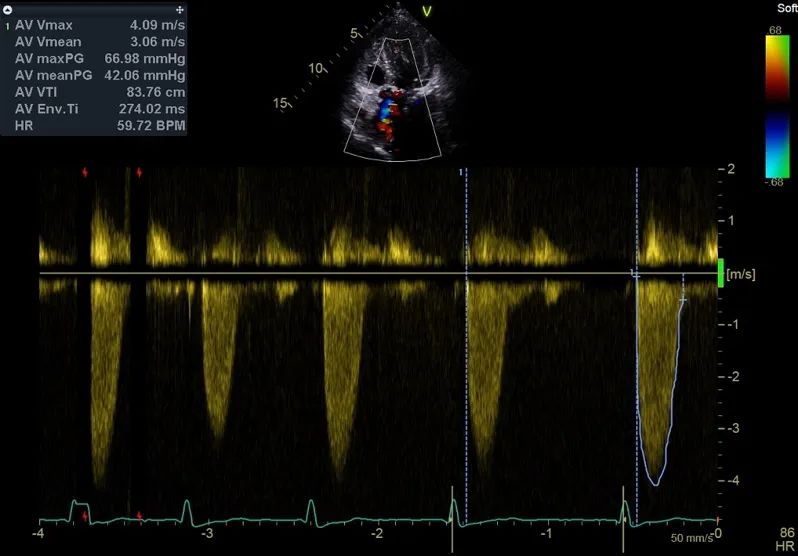

多普勒超声显示其流速和压差达重度狭窄

患者同时伴有二尖瓣退行性改变伴中度反流,左室肥厚,心腔较小(舒张末期室间隔厚度17.3mm,左心室舒张末期内径 36.3mm), EF为 63.6%。左室长轴整体应变率为-6.5%,提示其左室功能严重减退,同时伴有右房增大,右室收缩功能减低。